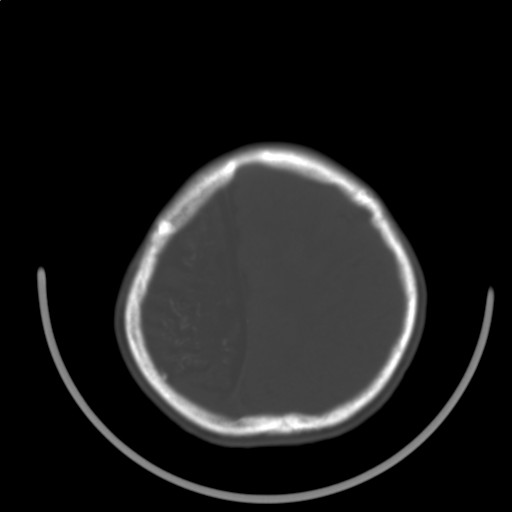

标题: PED3416:F,12Y,智力下降,学习成绩差,8个月时发过高烧。

右侧半球萎缩,软化,多量脑回样钙化,考虑颅面血管瘤病,建议dsa检查

右侧半球萎缩,软化,多量脑回样钙化,同侧颅盖板障增宽,考虑颅面血管瘤病,建议dsa检查与化脓性脑膜炎后遗改变鉴别。